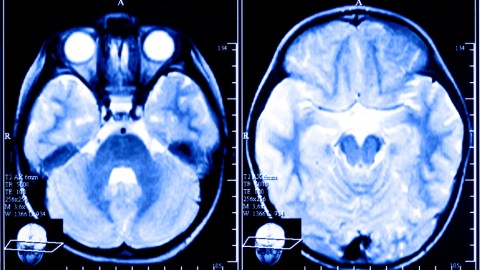

It’s possible to create brain patterns associated with affection and tenderness, using neurofeedback while someone is scanned in a functional magnetic resonance (fMRI) machine. The latest research has taken place in Brazil. “While lying in an fMRI machine, subjects were asked to think of memories of affection and pride while viewing a screen with a circle. The researchers used pattern-detection algorithms called ‘support vector machines’ to classify patterns in the participants’ brains. When these patterns were detected, the circle would ripple and change shape. (It didn’t change for the control group.)”